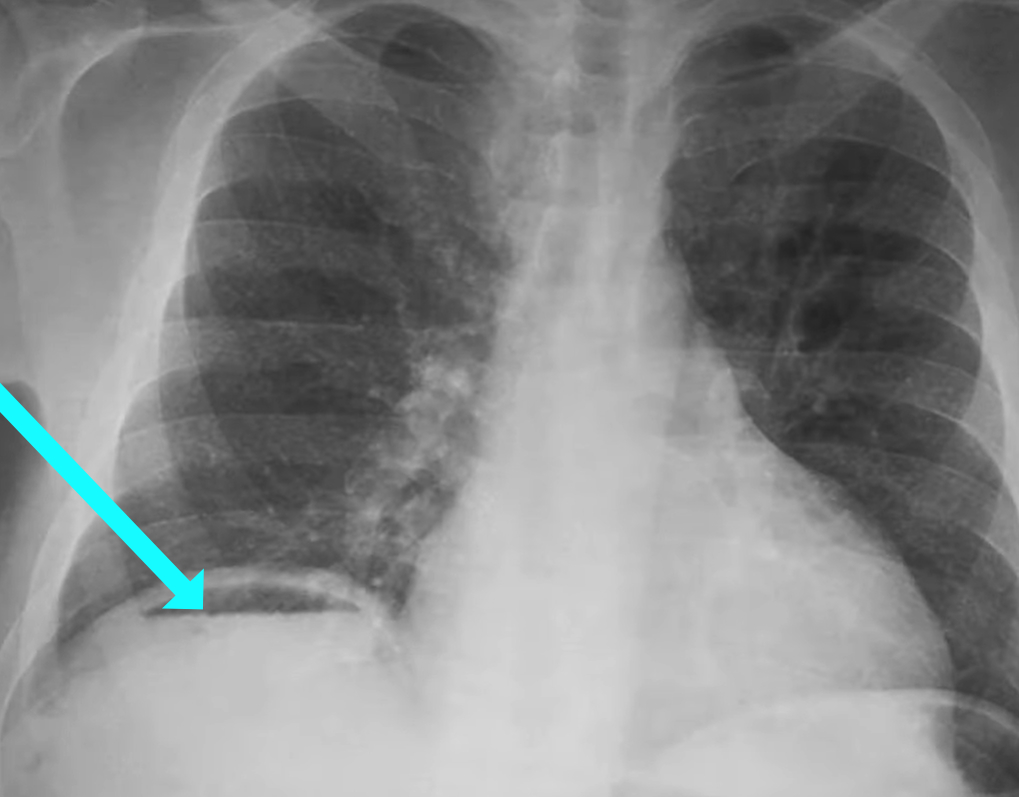

To what structure is the arrow pointing?

A) Liver

B) Kidney

C) Air fluid level

D) Water fluid level

Correct Answer: